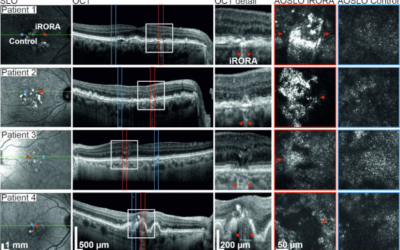

Detección temprana de la pérdida de visión en la degeneración macular relacionada con la edad (DMAE)

Detección temprana de la pérdida de visión en la degeneración macular relacionada con la edad (DMAE) Los datos podrían permitir nuevas terapias y mejores tratamientos. Una nueva investigación del Hospital Universitario de Bonn (UKB), en colaboración con la Universidad...